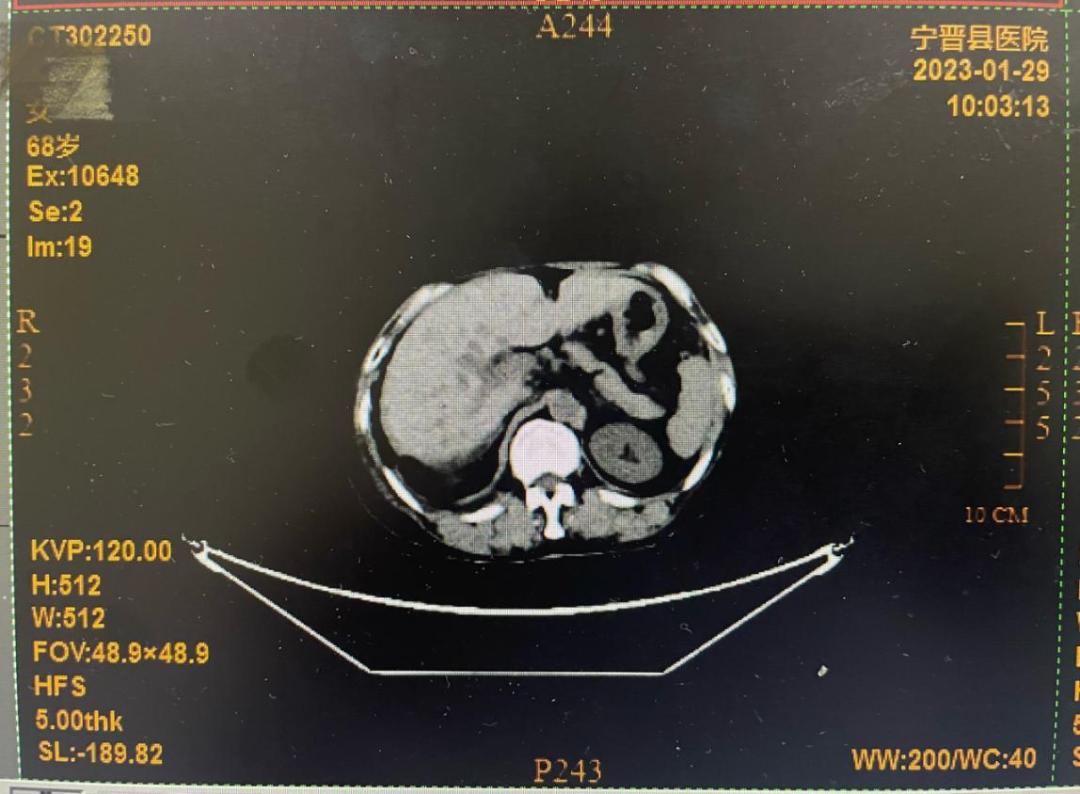

还有一位是68岁的患者文某,2021年初次来县医院肿瘤科就诊并确诊为胸膜恶性肿瘤;2023年1月因腹腔积液再次来院复诊,主管医师为其制定了个体化的化疗和热疗方案。一疗程后,CT显示腹水明显减少,患者主诉腹胀减轻。